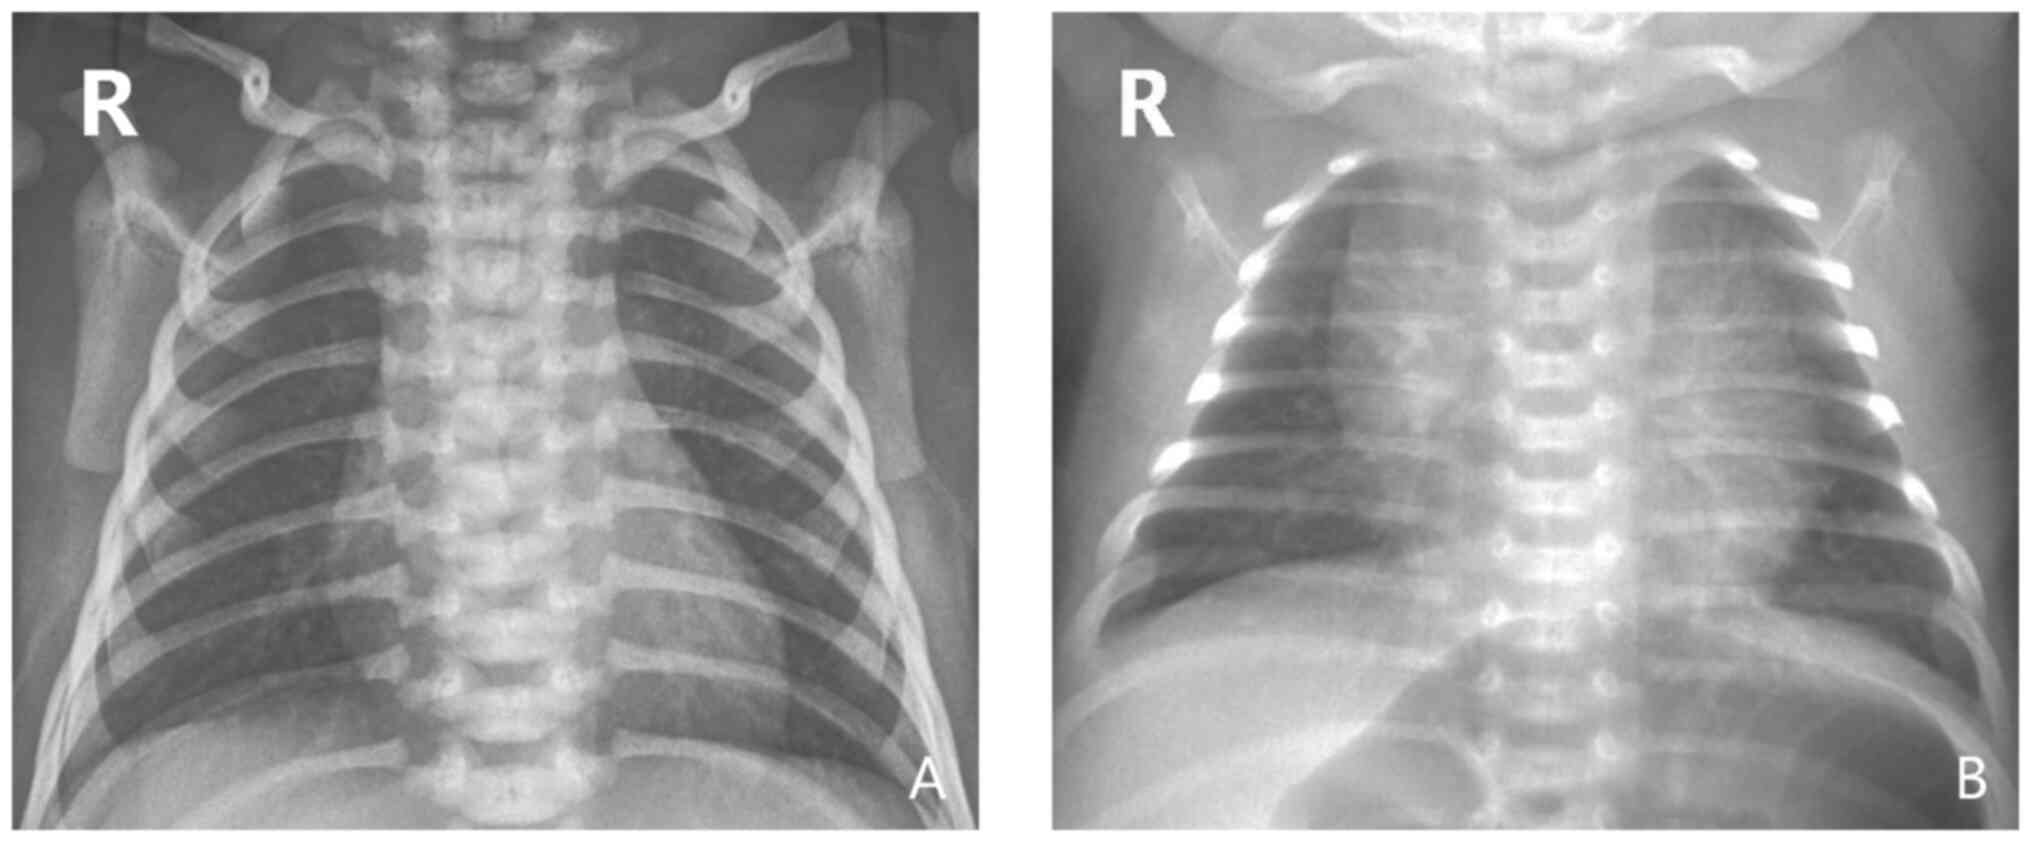

In total, 286 neonates were RSV-Ag-positive. Among them, 102 (35.7%) cases were positive (+), 138 (48.3%) were positive (++), and 46 (16%) cases were positive (+++). There were no significant differences in the degree of RSV-Ag positivity between the treatment and the control groups (Table II). Of the 286 cases, 191 (66.8%) were positive for bacterial co-infection (sputum bacterial culture), including those with Escherichia coli (21.5%, 41/191), Klebsiella pneumoniae (20.4%, 39/191), Staphylococcus aureus (17.2%, 33/191), Acinetobacter baumannii (13.1%, 25/191) and Pseudomonas aeruginosa (9.9%, 19/191). However, there were no significant differences in sputum bacterial culture-positive rate and bacterial spectrum between the two groups (P>0.05; Tables III and IV). There were 269 cases (94.1%) with abnormal chest X-ray findings, including blurred pulmonary texture, hyperinflation and visible flocculent shadow in the middle and inner side of the lung (Fig. 2). However, there was no significant difference in the positive rate of chest X-ray findings between the two groups (P>0.05; Table III).

Figure 2

(A) Representative chest X-ray of a normal, non-infected neonate. (B) Representative chest X-ray of a neonate with RSV pneumonia, the primary manifestations of which include blurred lung texture, hyperinflation and flocculation in the middle and inner lung. RSV, Respiratory syncytial virus.

RSV is one of the most common pathogens associated with infant respiratory tract infection. In the present study, the RSV-Ag-positive rate was 35.8%, suggesting that RSV is one of the primary causative agents of neonatal pneumonia. Infantile RSV pneumonia is largely characterized by symptoms such as high fever, marked dyspnea and wheezing; however, the symptoms and signs of neonatal RSV pneumonia lack specificity (35). In the current study, the key clinical manifestations of RSV pneumonia in neonates were cough, tachypnea, choking on milk, perilabial cyanosis and moist rales, accounting for 93.0, 90.9, 62.9, 67.8 and 58.4% of the total cases, respectively. The majority of the patients exhibited a normal temperature or low fever, and wheezing was not prominent. Therefore, it is difficult to distinguish RSV from non-RSV pneumonia according to clinical manifestations only. In the present study, the RSV-positive rate according to chest X-ray examination was 94.1%, and the key manifestations were blurred lung texture, hyperinflation and flocculation in the middle and inner lung. There were no significant differences in chest X-ray findings between neonates with RSV pneumonia and non-RSV infection, and the specificity was poor (36). Therefore, in the epidemic season, neonates with cough, tachypnea, choking on milk (amongst other clinical manifestations) should be more vigilantly assessed, and a more definite diagnosis of RSV should aim to be achieved.